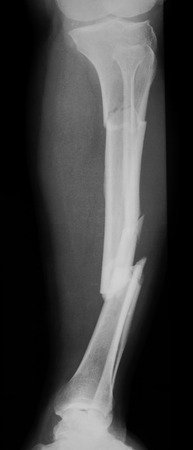

El crurifragium, o fractura de piernas, fue un acto despiadado llevado a cabo por los soldados para acelerar la muerte de los dos crucificados junto a Jesús, para que no quedaran los cuerpos en la cruz el sábado, nos dice San Juan (Jn 19, 31). Sucede que los crucificados, estando como estaban en esa dolorosísima posición, para poder respirar debían apoyarse sobre sus propios pies clavados para poder tomar aire, de allí que, para acelerar la muerte, muchas veces se les rompiesen las rodillas sobreviniendo así la asfixia. Fue así que se nos dice de Jesús, que «al ver que ya había muerto, no le quebraron las piernas, sino que uno de los soldados le traspasó el costado con la lanza…» (Jn 19, 33- 34) lónke autou, con su lanza, dice el original griego. Sabemos que la lónke, lanza con punta de hierro, formaba parte de la dotación de las tropas auxiliares en las provincias romanas. Luego vendrá la sepultura.